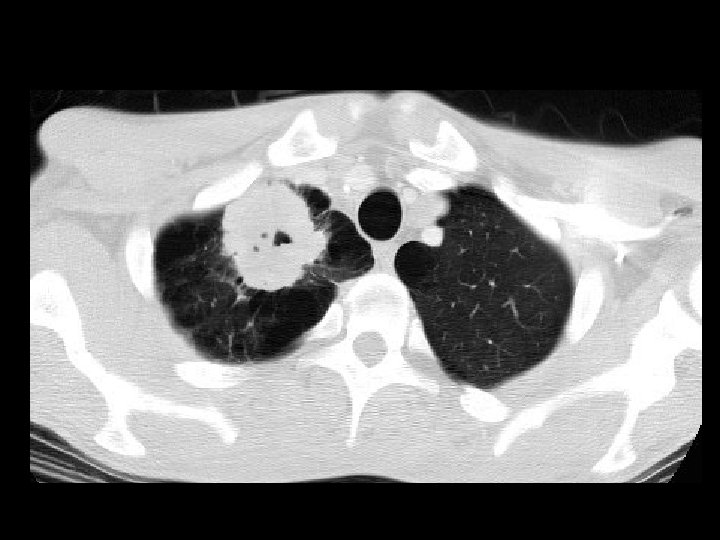

Squamous cell carcinoma • Findings: – Spiculated mass in the RUQ – necrotic center – background of emphysema • ddx: – TB – metastasis